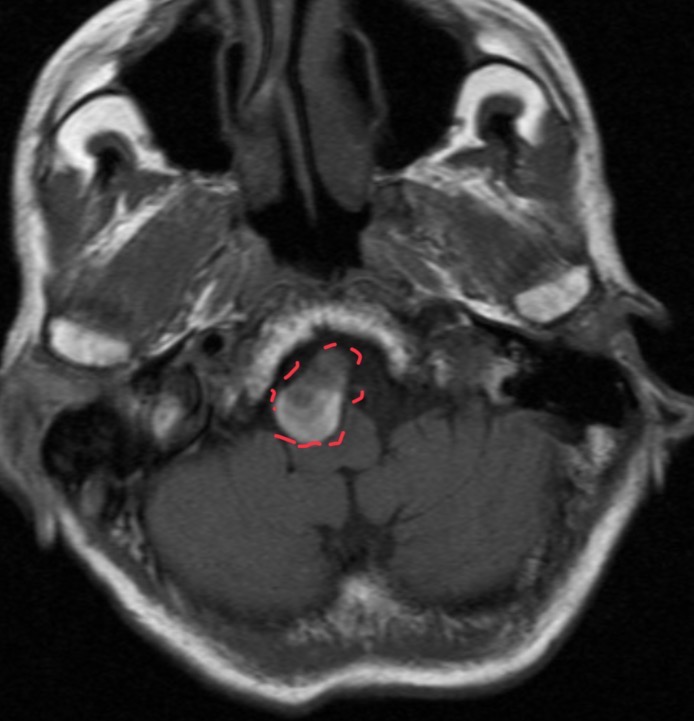

Child presents with no available information

Retinoblastoma w retinal detachment